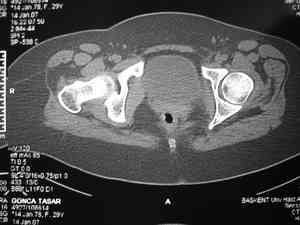

Dear group, 30 years age female MVA front seat, head trauma + post column left acetabular fracture, 2.5 weeks skeletal traction. She is now conscious but still confused without any surgical treatment for brain edema.

Latest X rays and CAT is attached. Fracture within first 1.5 cm from the weight bearing dome, although AP and Obtrator oblique good, iliac oblique view reveals some displacement. I'm not sure that nonsurgical treatment will be OK Hüseyin Demirors Baskent University Dept of Orthopedics and Travmatology Ankara TURKEY